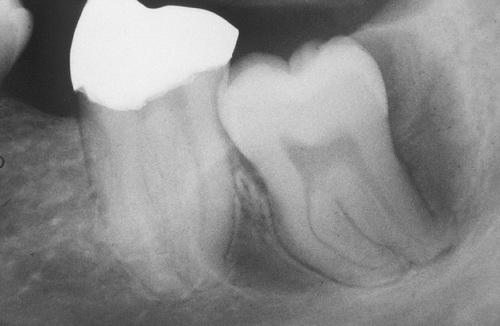

A small unilocular radiolucency associated with the impacted mandibular left third molar. Histopathologic examination shows a lining of orthokeratotic stratified squamous epithelium.

orthokeratinized odontogenic cyst

A large cyst involving a horizontally impacted lower third molar. Histopathologic examination shows a lining of orthokeratotic stratified squamous epithelium.